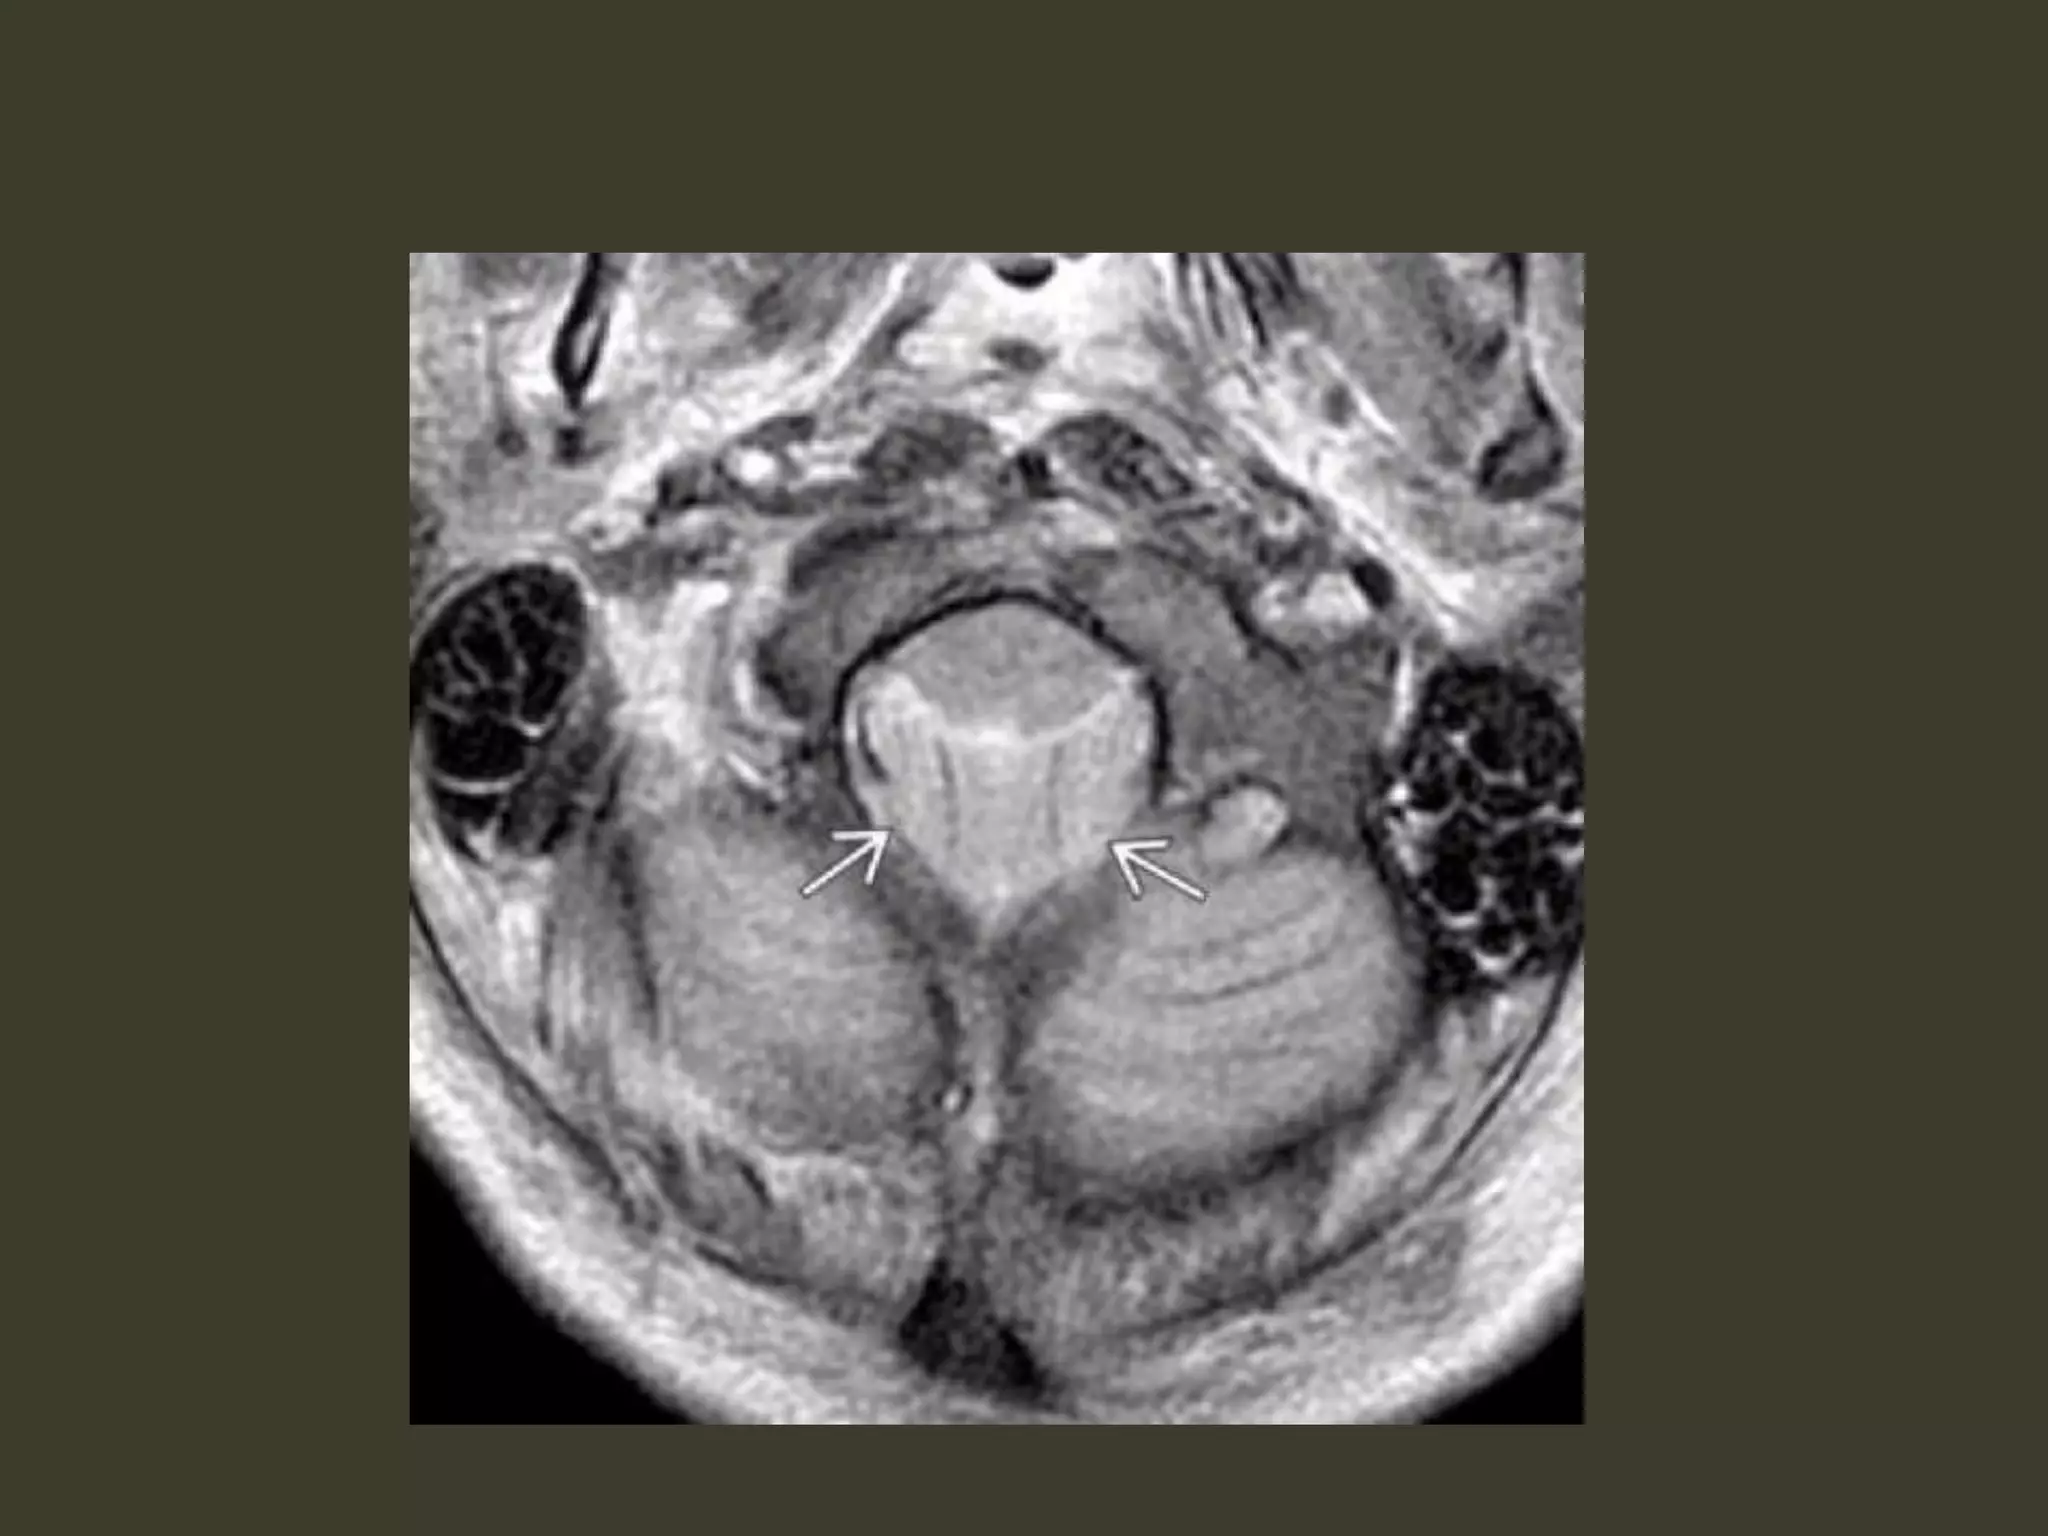

Tonsillar herniation: imaging

• Diagnosing tonsillar herniation on NECT scans

may be problematic.

Cisterna magna obliteration

• MR: much more easily diagnosed

• In the sagittal plane

– the tonsillar folia become vertically oriented

– the inferior aspect of the tonsils becomes

pointed

– Tonsils > 5 mm (or 7 mm in children) below the

foramen magnum are generally abnormal

• especially if they are peg-like or pointed (rather than

rounded)

• In the axial plane, T2 scans show that the

tonsils are impacted into the foramen

magnum

– obliterating CSF in the cisterna magna

– displacing the medulla anteriorly